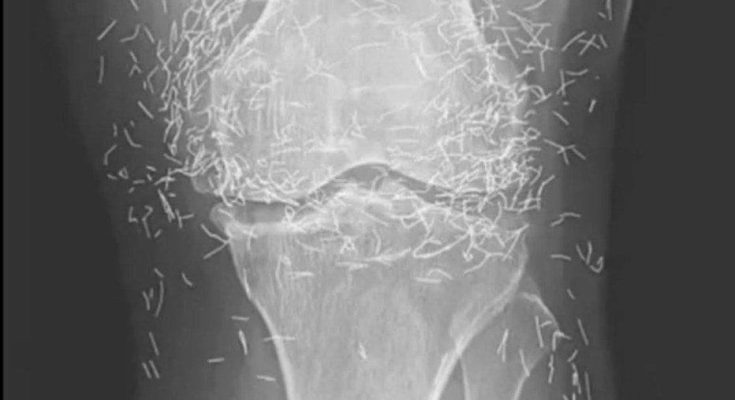

Years later, when doctors took X-rays to evaluate her knee condition, they weren’t prepared for what appeared on the images. Her knees were filled with dozens of bright, metallic flecks — tiny needles embedded deep within the joint area.

The findings were later documented in a case published by the New England Journal of Medicine.

Beyond inflammation, the needles created another problem: imaging complications. Metal objects can obscure parts of the anatomy on X-rays, making it harder for doctors to clearly assess joint damage or disease progression.

Even more concerning, the presence of metal inside the body can make certain scans dangerous. MRI machines rely on powerful magnetic fields, and embedded needles may shift during scanning, potentially damaging blood vessels or surrounding tissue. In short, future diagnostic options for this patient became limited.